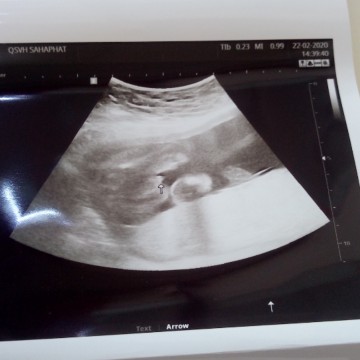

ผู้หญิงค่ะแม่😘